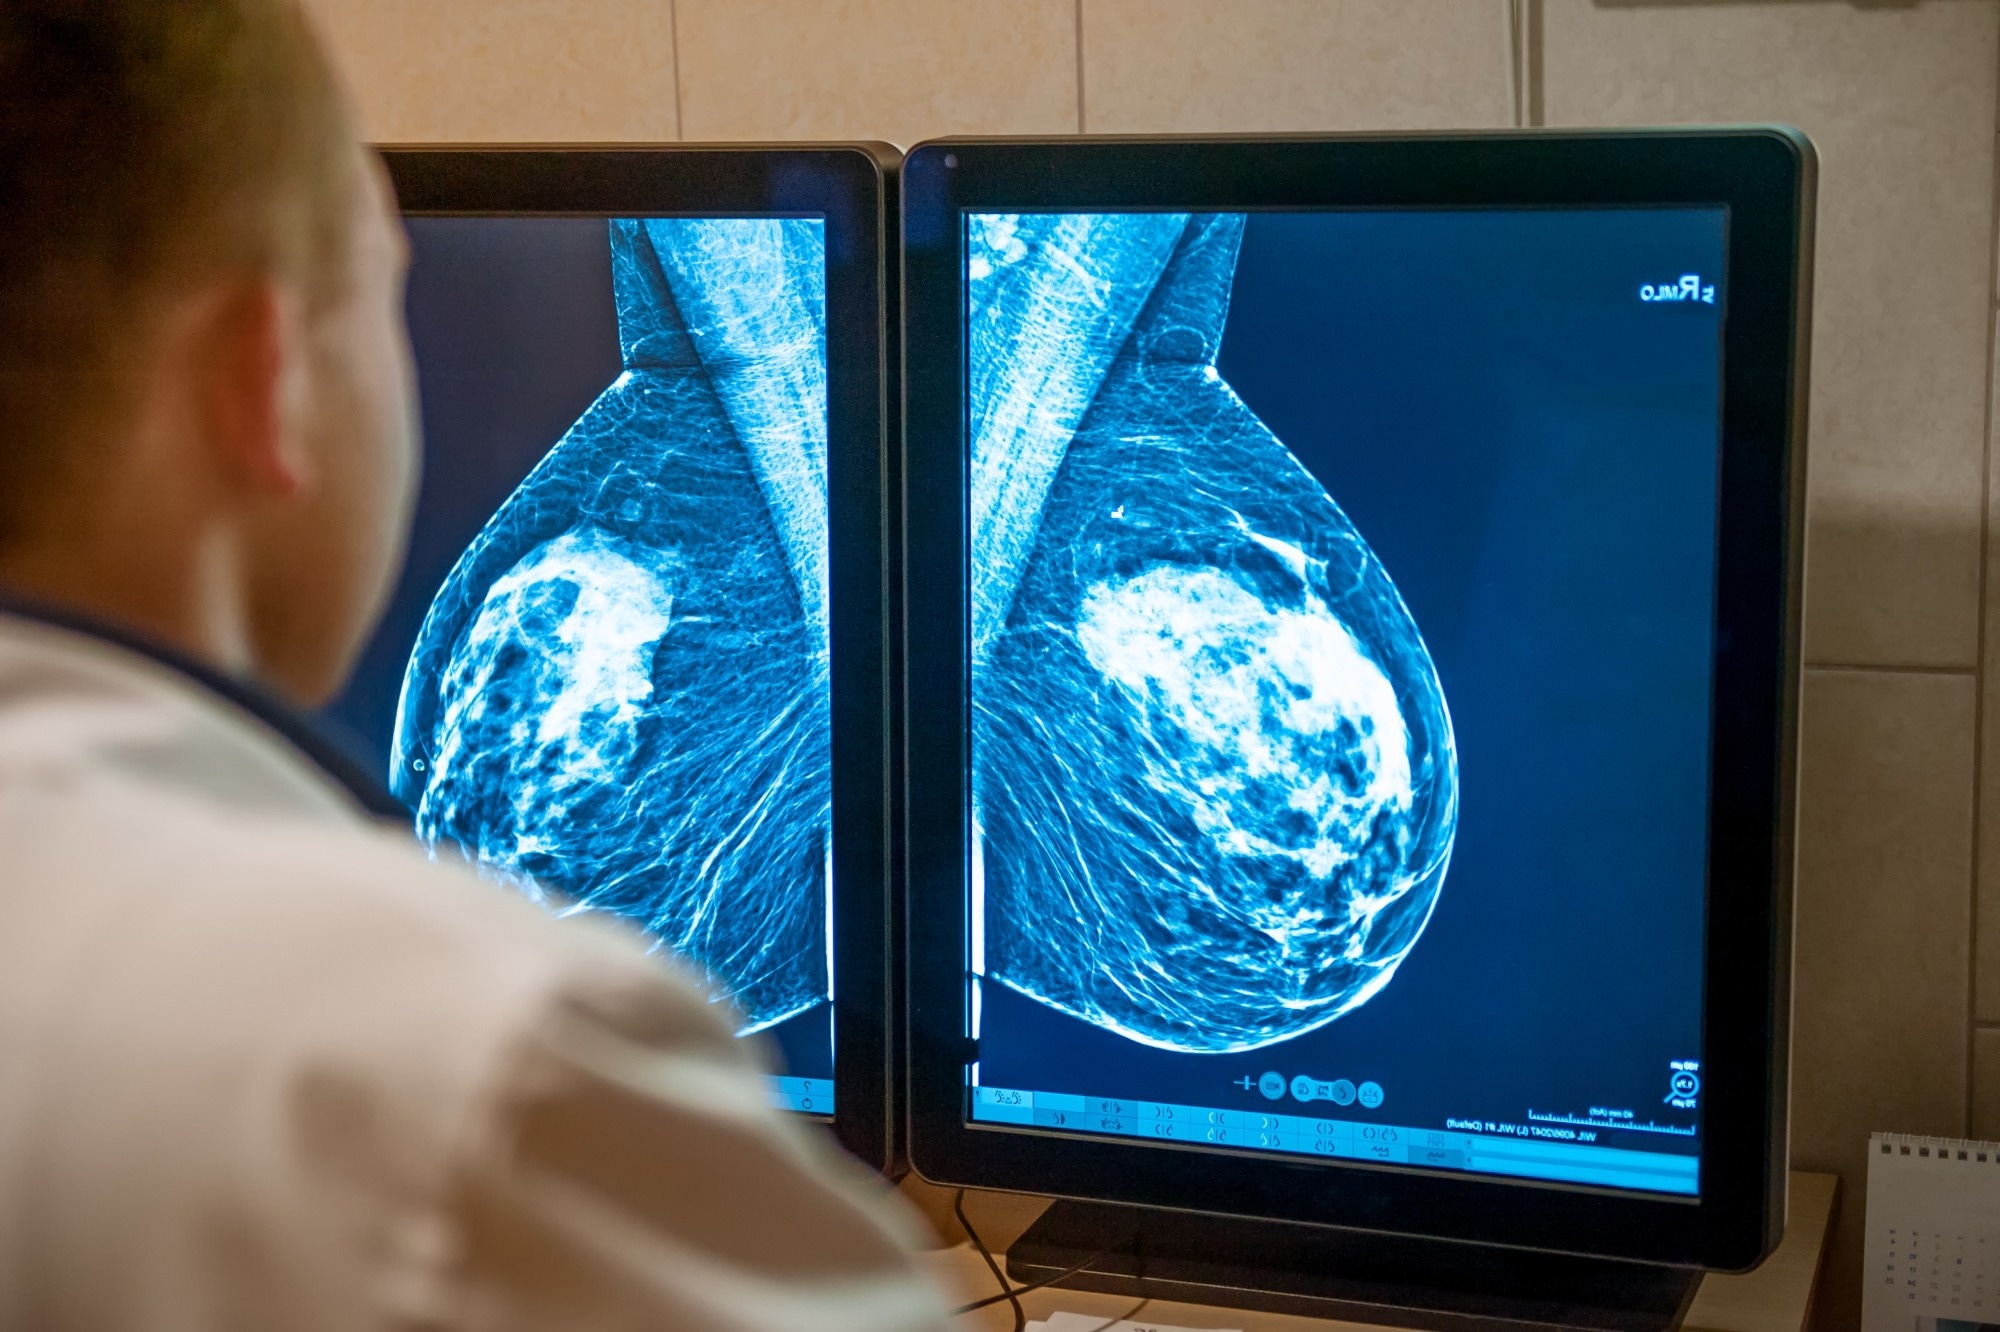

Study: Sociodemographic variations in women’s reports of discussions with clinicians about breast density. Image Credit: Okrasiuk / Shutterstock.com Study: Sociodemographic variations in women’s reports of discussions with clinicians about breast density. Image Credit: Okrasiuk / Shutterstock.com

Since breast density affects the results of screening mammography and independently poses a risk factor for breast cancer, it is important that women discuss this factor with their doctors. To facilitate these conversations, it is mandatory in many American states that dense breasts be identified clearly and women are notified following mammography.